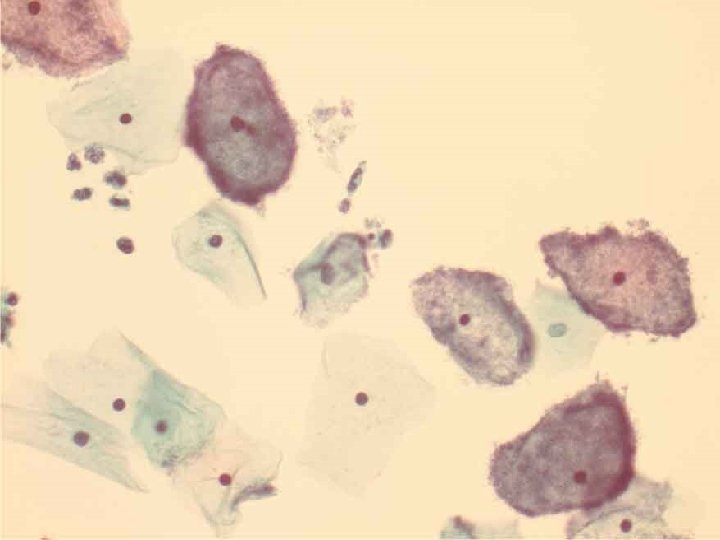

Особенности метода жидкостной цитологии • Препарат представляет собой «усредненный» клеточный состав • Желательно окрашивать препараты по Папаниколау или гематоксилин-эозином • При окрашивании методом Романовского (Паппенгейма, Лейшмана и др. ) плохо видна структура ядра